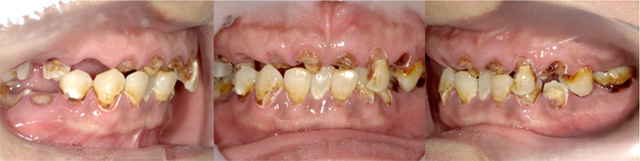

当院で治療された方の症例集をご覧ください!

オールオン4の治療例:1

治療前

治療後

オールオン4の治療例:2

その他 ボロボロ虫歯の症例